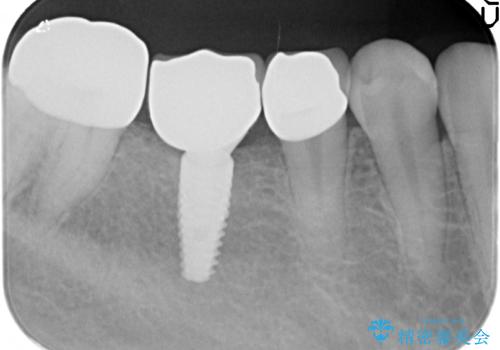

保存可能な歯の虫歯・根管治療を行い、喪失した部分はインプラントを埋入、オールセラミックジルコニアクラウンを製作し審美的に仕上げていきます。

- 120万円(仮歯×6・ファイバーコア×2・ジルコニアクラウン×6・インプラント×2・チタンカスタムアバットメント×2)費用は治療当時の料金となります

今回下顎の欠損部位はブリッジも検討されましたが、並行性の観点から最後方臼歯の神経を取るリスクを抑えるためインプラント治療を選択しました。